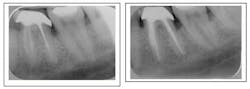

Iatrogenic error

The delicacy of root canals make iatrogenic events an unfortunate occurrence. The question the clinician must ask when presented with a failing case due to iatrogenic error is: Is it repairable?

Perforations can often be repaired and, depending on the size of the periodontal communication, may be successful. Coronal perforations have a worse prognosis when compared to those more apically. However, time is of the essence in treatment, and often when a perforation has persisted long term, the prognosis is unfavorable. (Wong, 1997)

Ledge formation, commonly referred to as a blocked canal, is an iatrogenically created irregularity that impedes instruments from achieving patency to the root end. In many cases, the apex is insufficiently debrided. Blocked canals may result in failing root canals due to persistent infection that remains untreated. If adequately skilled and if lucky, the clinician may be able to regain patency by precurving a file. Sometimes these cases can only be retreated by surgical removal of the root end. (Wong, 1997)

Transportations can be a result of a ledge formation. It is a false canal that does not follow the natural root anatomy. Unless there is a second canal, as in the mesial root of an upper molar or distal root of a lower molar, the chance of regaining access to the true canal is minimal. If these cases fail, they are best treated by extraction or a combination of retreatment and surgery, as is discussed below. (Wong, 1997)Strip perforation (coronal third of root) repair with MTA. Patient had a draining sinus tract into furcation. With perforation repair, sinus tract healed.